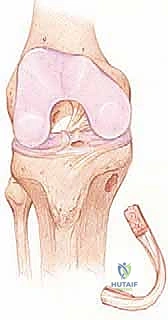

في مركز الأستاذ الدكتور محمد هطيف الرائد في صنعاء، لا ننظر إلى تمزق الرباط الصليبي كمجرد إصابة جسدية، بل ندرك تماماً الأثر النفسي والوظيفي العميق الذي تتركه هذه الإصابة على حياة المريض. تقنية إعادة بناء الرباط الصليبي الأمامي التي نعتمدها تهدف إلى استئصال البقايا المتمزقة واستبدالها بطعم نسيجي قوي (Graft)، يتم تثبيته داخل أنفاق عظمية دقيقة في عظمي الفخذ والقصبة، ليستعيد المفصل ثباته، ويحمي الغضاريف الهلالية من التمزقات الثانوية التي غالباً ما تصاحب الإهمال في علاج هذه الإصابات.

تقنيات جراحة إعادة بناء الرباط الصليبي الأمامي وأنواع الطعوم

لا يمكن خياطة الرباط الصليبي الأمامي المتمزق (إلا في حالات نادرة جداً لتمزقات معينة عند نقطة الاتصال العظمي). لذلك، يجب "إعادة بناء" (Reconstruction) الرباط باستخدام نسيج بديل يُسمى "الطعم" (Graft).